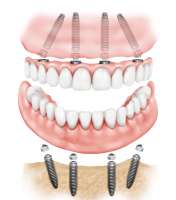

Анон, у меня тяжёлый случай. Большинству зубов полная гнилая пизда, и фоткой моего рта можно сагать неугодные треды; больше половины рта надо вынимать и вставлять импланты.

Расскажи, пожалуйста, про такую тему как all-on-4 (all-on-6 итп), а точнее про её минусы, подводные камни и неочевидности (про плюсы мне и реклама расскажет).

Есть тут те, кто через это прошёл?

Реально работает или наебалово?

Четыре винта в самом деле держат ебейшую жевательную нагрузку? Оно не отвалится через полтора года грызения орешков?

Вероятность отторжения больше/меньше, чем у обычных имплантов? Требует ли какого-то хитровымученного обслуживания?

Я не приму ислам, от того, что мне вынут все мои 30 гнилых пеньков?

На каком-то из сайтов клиник читал, что они дают "пожизненную гарантию", значит ли это, что эта штука убьёт меня быстрее, чем закроется клиника?

Да работает. Импланты , в данном случае выполняют роль больше как для фиксации протеза. Если твои пеньки не слишком гнилые , то могут использовать и их даже. Но если они не настолько гнилые, то можно восстанавливать обычными мостами\единичками без необходимости ставить полные съемные протезы.

Про all-on-4 потому и спрашиваю, что оно дешевле, и на это 300-600К бабла, вроде, кое-как наскрести можно попробовать. Но ссу того, что дешевый сыр бывает в мышеловке.